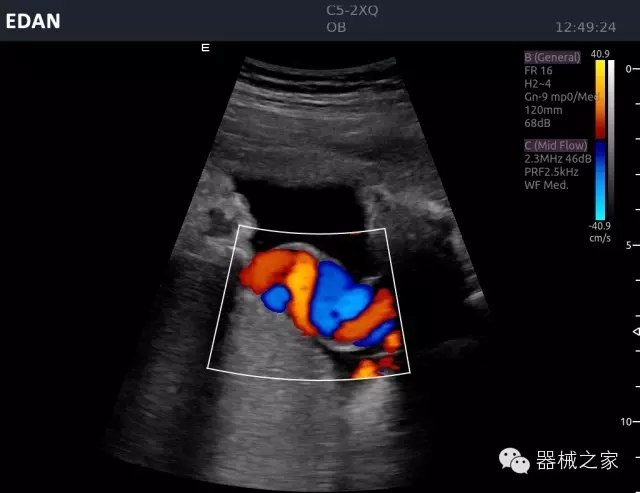

品牌:理邦儀器(EDAN)

經(jīng)典產(chǎn)品:Acclarix AX8

臨床圖片賞析

睪丸低速血流

臍帶血流